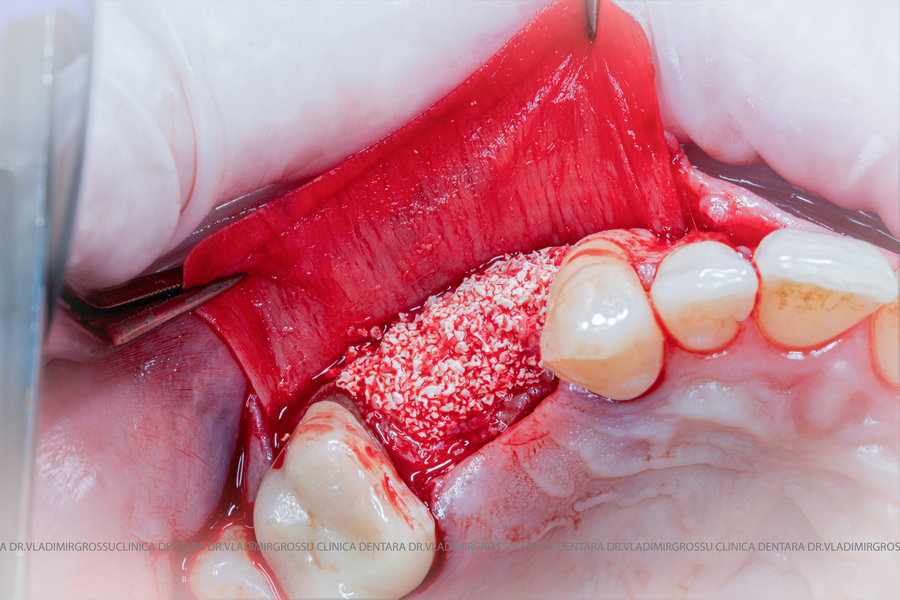

Cele mai utilizate patru categorii de materiale, în funcție de origine, sunt:

- Autogrefe — os propriu, recoltat de la pacient;

- Alogrefe — os uman prelucrat, recoltat de la donatori vii sau decedați;

- Xenogrefe — os de origine bovină;

- Materiale osteoplastice sintetice — cu avantaje și limitări specifice.

Un element esențial în procedura de aditie osoasă este utilizarea membranelor biologice, care izolează materialul osos de țesuturile moi (gingie) pe durata procesului de vindecare. Cele mai recomandate sunt membranele resorbabile din colagen sau pericard.